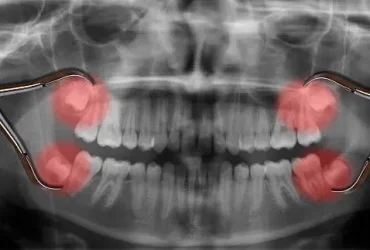

ฟันคุดคือ อะไร

ฟันคุดคือ ฟันกรามซี่ในสุด ทั้งหมด 4 ซี่ บน ล่าง ซ้าย ขวา ไม่สามารถขึ้นได้ตามปกติเพราะพื้นที่ไม่เพียงพอให้ฟันสามารถขึ้นมาได้ บางซี่อาจจะโผล่ขึ้นมาเล็กน้อย และบางซี่ถูกฝั่งอยู่ในกระดูดขากรรไกร อาจจะขึ้นตรง เอียงหรือนอนในแนวราบส่วนใหญ่ฟันคุดมักพบว่าอยู่ที่ฟันกรามซี่ล่างในสุดและพบมากสุดในช่วงอายุ ประมาณ 16 – 25 ปี หรืออาจจะช้ากว่านั้น

ทำไมต้องผ่าฟันคุด

เพื่อป้องกันปัญหาเกี่ยวกับช่องปาก ฟันผุ เหงื่อกอักเสบ ฟันซ้อมเก ไม่ควรปล่อยให้ฟันคุดฝั่งอยู่ในขากรรไกร เพราะอาจะทำให้แนวฟันอื่นเสียหายจากการดันตัวของฟันคุด และที่สำคัญคือส่งผลให้มีอาการปวดฟันคุดรุนแรง